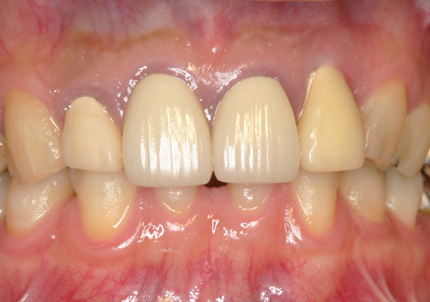

22.最終補綴物完成・装着口腔内写真(2021年1月)

23.自然な形態のインプラント歯頚部

適切な治療計画と治療技術を有することで、このような自然な形態のインプラント歯頚部を形成することができます。

24.口腔内写真

【 2018年 術前 】

【 2025年5月 現在 】